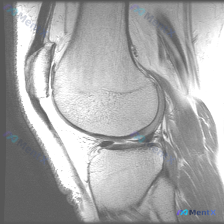

看到这个很有代表性的病例,整理出来和大家分享一下。 病例基本信息 临床提示:患者考虑存在膝关节软骨异常 影像资料:单张膝关节MRI矢状位T1WI图像 本次影像系统分析结果 先给大家说下这份影像的具体观察结果: 1. 序列与层面确认:这是标准T1WI矢状位,骨髓高信号、积液低信号,解剖结构对比清晰,图...